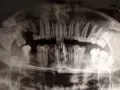

Удалили нижнюю правую восьмёрку, удаление было сложное. После залили, но через сутки начало опухать. Сходила к врачу, предложил почистить лунку. Швы сняли и зашивать больше не стали, положили в рану марлю с каким-то лекарством. Через 5 дней вытащили ее. И вот, спустя сутки, что-то стало опять подергивать в ране (она почти срослась, но немного щель осталась).

Что это может быть: воспаление или так и должно заживать?